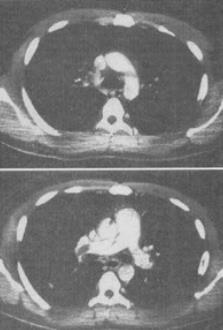

男,28岁,突发呼吸困难,结合图像,最可能的诊断是()。

C、右主肺动脉栓塞

C